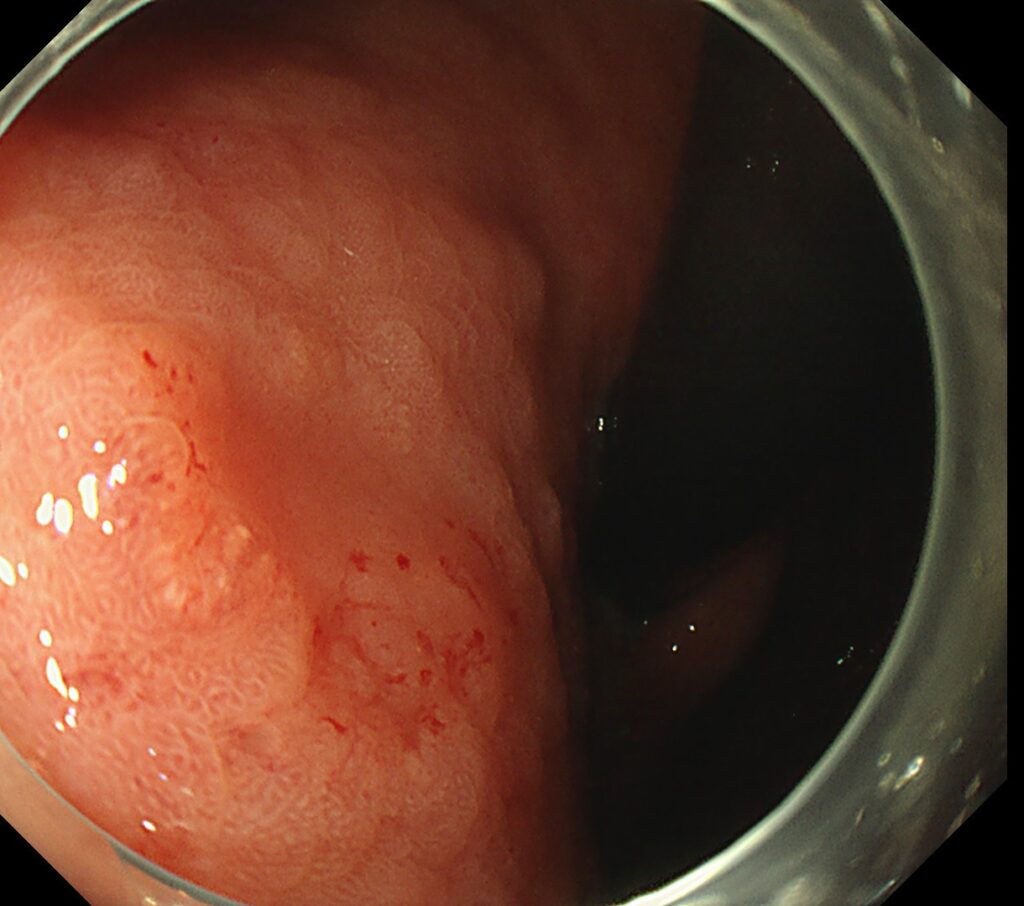

穿通するほどですので、胃は強く変形しており、わかりやすい写真がとれず・・・。

付図のごとく、胃の小彎側に、突如ひだが途絶するほどの潰瘍瘢痕を認めます。

その直上に

易出血性の陥凹性病変を認めます。